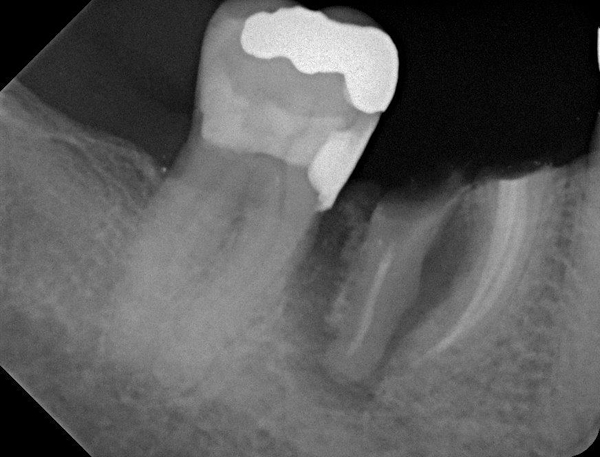

Fig 23. Implant inserted in a regenerated ridge after 6 months healing.

Figure 23

Fig 24. Cone beam scan demonstrating bone circumferentially around the dental implant.

Figure 24

Fig 25. Radiograph showing appearance of restored implant after 1 year.

Figure 25